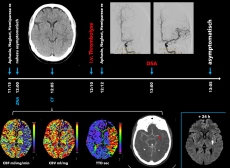

Patienten und Patientinnen mit einem akuten Schlaganfall werden durch das Team der Zentralen Notaufnahme diagnostiziert und den Akuttherapien zugeführt – der intravenösen Thrombolyse und, bei großen Gefäßverschlüssen, der endovaskulären Thrombektomie durch die Neuroradiologie (Abbildung 2). Anschließend übernimmt ein spezialisiertes Team aus vaskulären Neurologen und Neurologinnen, Pflegepersonal sowie Therapeuten und Therapeutinnen (Ergotherapie, Logopädie, Physiotherapie) die Behandlung auf der Stroke Unit. Aufgabe der Stroke Unit ist es, zum einen optimale sekundärpräventive Maßnahmen zu ergreifen um ein Rezidiv zu verhindern, zum anderen neurologische Defizite frühestmöglich umfassend zu behandeln und, wenn notwendig, anschließende Rehabilitationsmaßnahmen vorzubereiten.